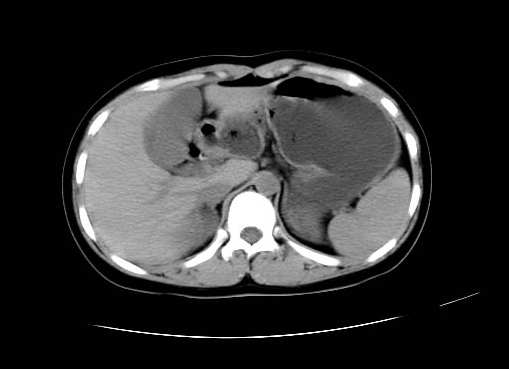

女 16岁  右上腹痛一天,无其他不适

右下腹巨大肿快,密度不均匀,内见坏死低密度区,边界清楚,与周边胀器明显有分界,未见强化,多考虑来源于间叶组织的良性肿物.

病灶巨大,少部分向肠腔内生长,大部分向长腔外生长。其密度不均匀,增强显示明显不均匀强化,并见有大片状始终不强化的不规则坏死液化区。虽然病灶中上部形态尚可,病人又如此年轻,但中下部形态、密度、强化特点强烈提示为恶性病灶。综上,我考虑本病例为:恶性胃肠道间质瘤。